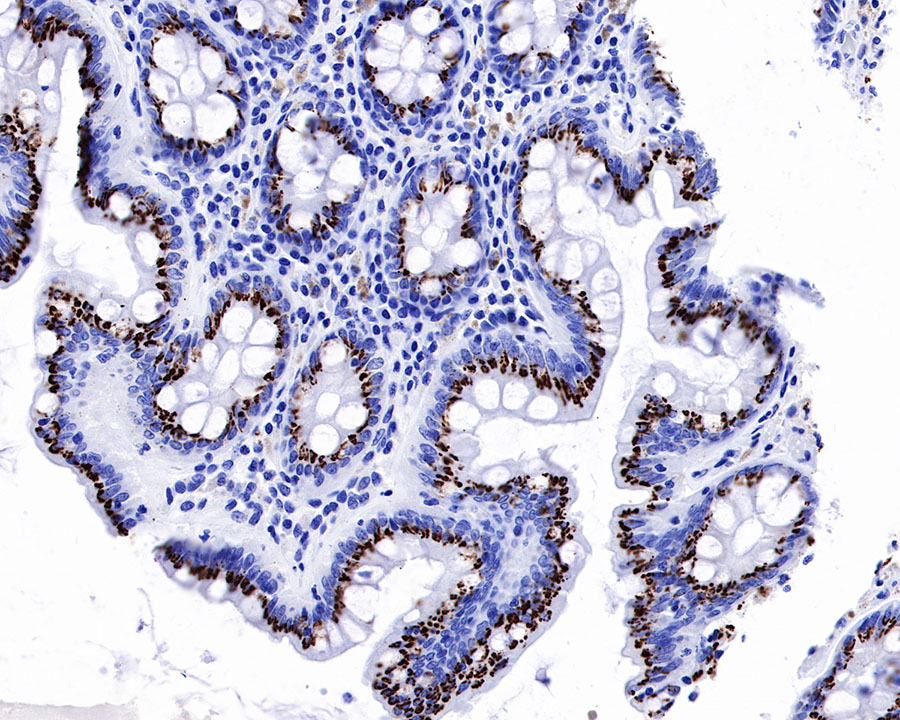

IHC shows positive staining in paraffin-embedded human colon. Anti-GP73/GOLPH2 antibody was used at 1/1000 dilution, followed by a HRP Polymer for Mouse & Rabbit IgG (ready to use). Counterstained with hematoxylin. Heat mediated antigen retrieval with Tris/EDTA buffer pH9.0 was performed before commencing with IHC staining protocol.